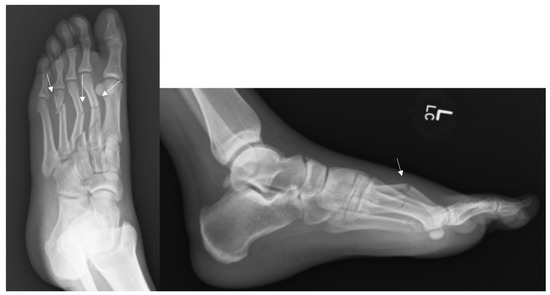

Figure 3.

Radiographs of a Metatarsal Fracture Displaced 3–4 mm. Displayed above are radiographs of a fifth metatarsal shaft fracture that is displaced between 3–4 mm. The arrows above identify the fifth metatarsal fracture.

Figure 4.

Radiographs of a Metatarsal Fracture Displaced Greater than 4 mm. Displayed above are radiographs of a fifth metatarsal shaft fracture displaced greater than 4 mm. The arrows above identify the fifth metatarsal fracture.